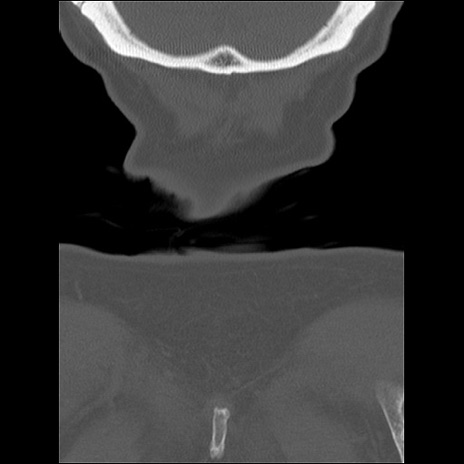

頚椎CT

横断像